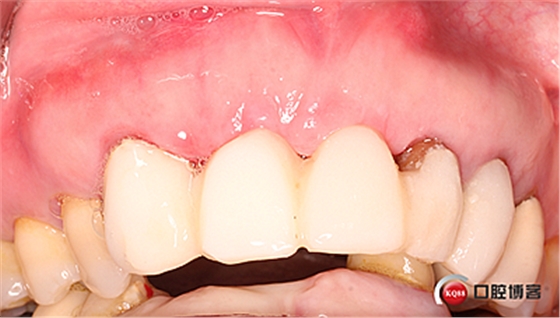

患者女性,52歲,缺失三顆牙,骨性前突,頜弓窄,身高175,魁梧,放了三顆牙是不是有點(diǎn)細(xì)?左上3開(kāi)膠了,牙體有腐蝕。

鄰牙重新備牙,制作臨時(shí)樹(shù)脂橋體,缺牙區(qū)三顆變?yōu)閮深w。下圖是術(shù)后一個(gè)月口內(nèi)照。

術(shù)后兩個(gè)月。

術(shù)后4個(gè)月,三顆牙變?yōu)閮深w牙齦乳頭改造是難點(diǎn)。